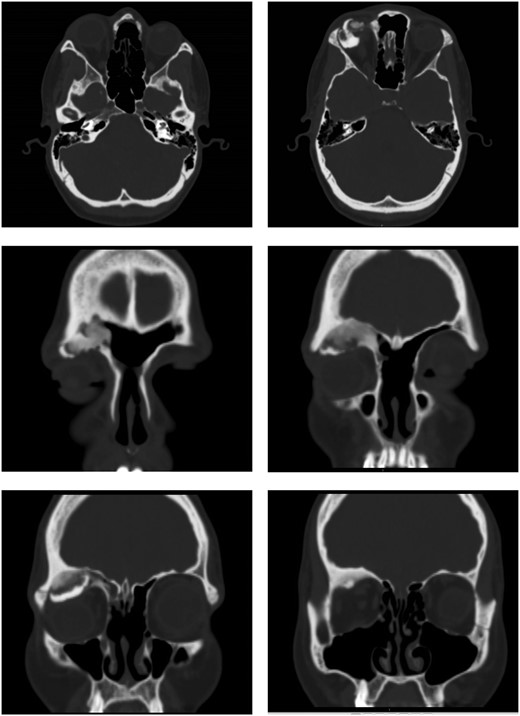

Computed tomography (CT) of the sinuses revealed proptosis, downward displacement and flattening of the upper surface of globe because of a recurrent right frontal sinus OF (Fig. 1).

Ossifying fibroma in the right frontal sinus involving anterior and lateral frontal sinus walls, and orbital floor.